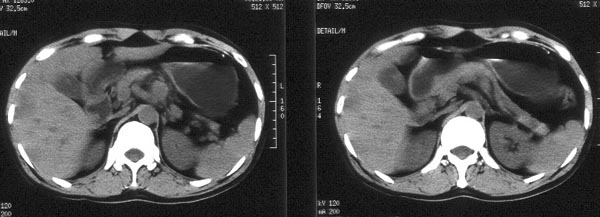

男性,46岁。腹痛月余。胃镜检查示“胃贲门区占位”,活检病理示

“胃贲门癌”。

ct平扫:胃贲门部见软组织肿物突入胃腔内,大小4x3cm,浅分叶状,中央密度较低,邻近胃壁增厚。外缘与周围组织分界清。im25层面,小网膜囊区见两枚肿大淋巴结,直径均约3cm。肝脏大小正常,肝内散在分布多个大小不等的类圆形低密度影,最大者位于肝右前叶上段,直径约4cm,病灶边缘模糊,与正常肝实质分界欠清。

ct诊断:胃贲门癌,并腹腔淋巴结转移及肝内多发转移。